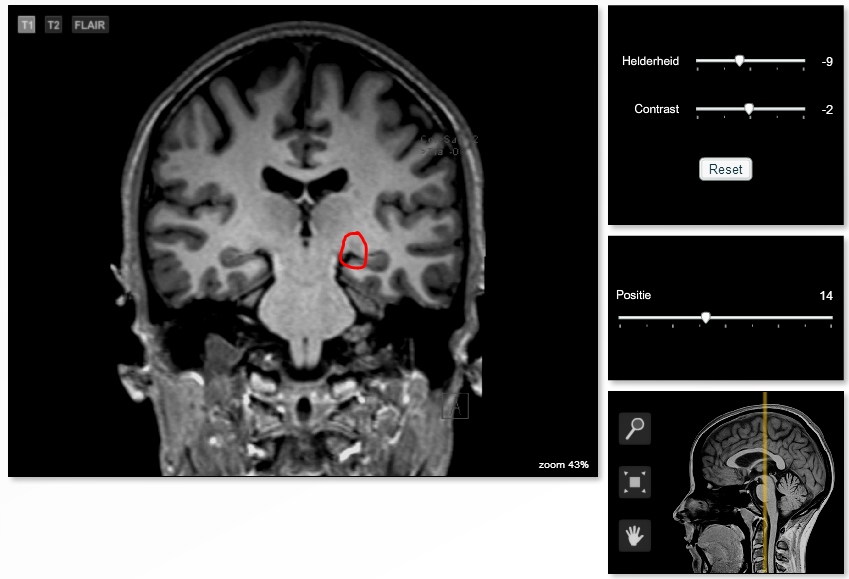

So what's the thing I put a circle around then on the image below? I would ask him, but suggesting that that would be the LGN would mean suggesting he is wrong. Should I be wrong, then it would be very much out of my place to suggest he is wrong. He's the radiologist, after all!

It's near the quadrigeminal plate (a bit more rostral and, of course, more lateral) which might suggest that that is indeed the LGN.

Thank you for your answer. Indeed, it is most probably the left LGN.

I kind of misunderstood him, interpreting that it could not be found on the scans given to us.

The message I misunderstood he tried to spread was that they failed to outline the LGN (they forgot it or whatever), so it could not be highlighted in the program we're using to see these scans, nor could it be found in the index with structures which can be highlighted :)